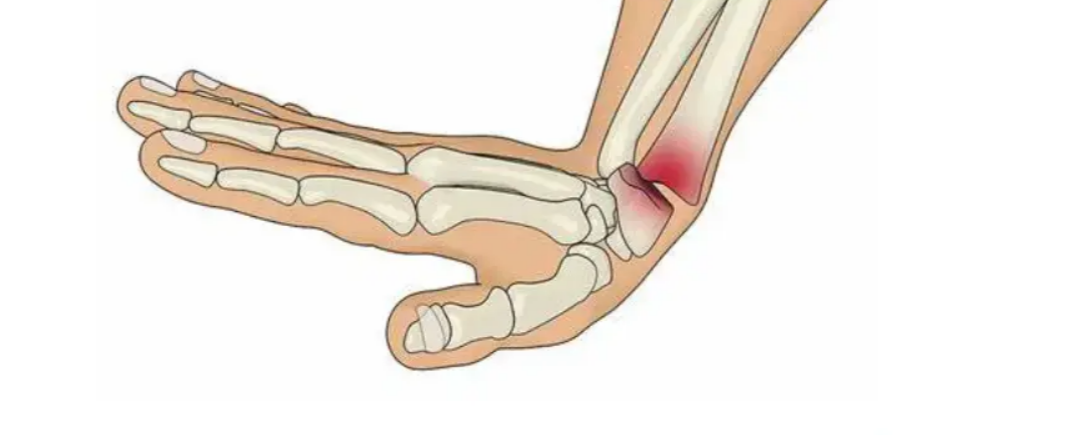

Bunion Or Hallux Valgus

Hammer Toe